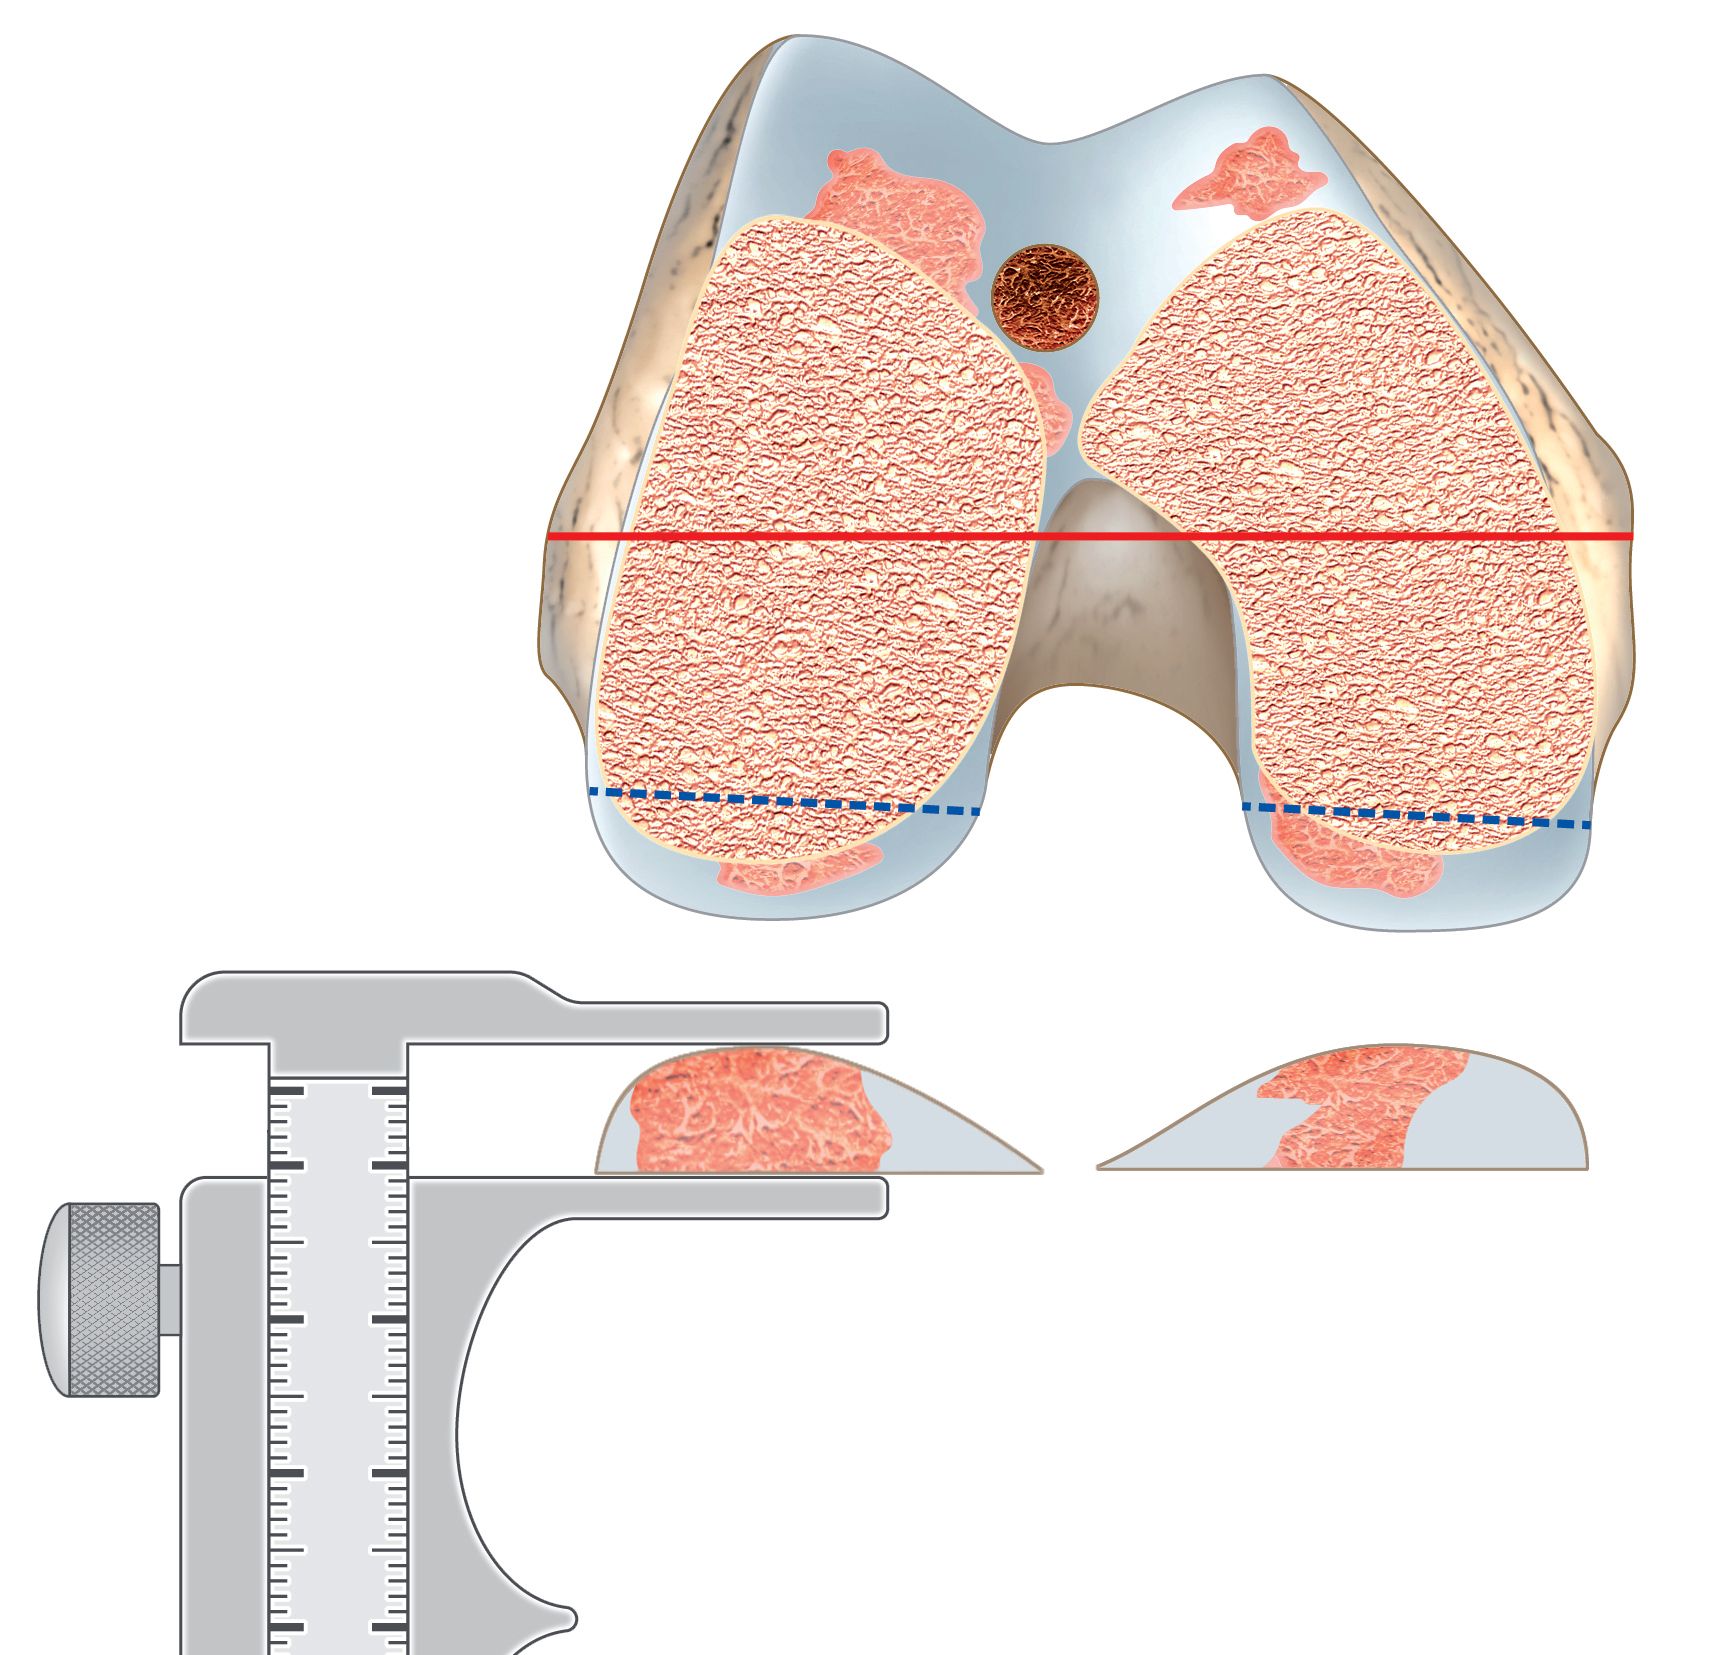

The problem are the axial plane deformities of the proximal tibia with the wide variation of the TT position to the proximal tibia anatomy [3,22,30,48] (Fig 23). For these cases none of the described techniques are perfect and they can make either the tibiofemoral joint or the patella tracking happy and it needs to find a compromise to correct this tibia axial plane deformities.

On standardized AP and lateral radiographs these axial plane deformities cannot be identified. The golden standard for the identification of proximal tibia axial plane deformities is still CT or MRI imaging (Fig 23 A and B) [5,30].

During surgery the proximal axial plane deformity of the tibia can be easily identified, by drawing the TTA of Insall and compare it with the mid-sulcus line, as described above (Fig 21). Any deformity greater than 5 mm should be corrected during surgery. There are four options to correct this tibia axial deformity.

8.2 Functional derotation inside the joint

By using the TTA of Insall and minimum PS constraint, the tibia will make an internal rotation with the trial components inside (Fig 25 A and B). This brings the TT under the trochlea and reduce the pathological TT-TG to less than 5 mm [34]. Sometimes the insertion of the PE insert is difficult and can be performed only by forced internal rotation of the lower leg. CR and mobile bearing inserts do not work with this technique. Maximum 30° of functional derotation is possible, otherwise the forefoot progression angle gets negative with internal rotation of the forefoot and the collateral ligaments tension is changed.